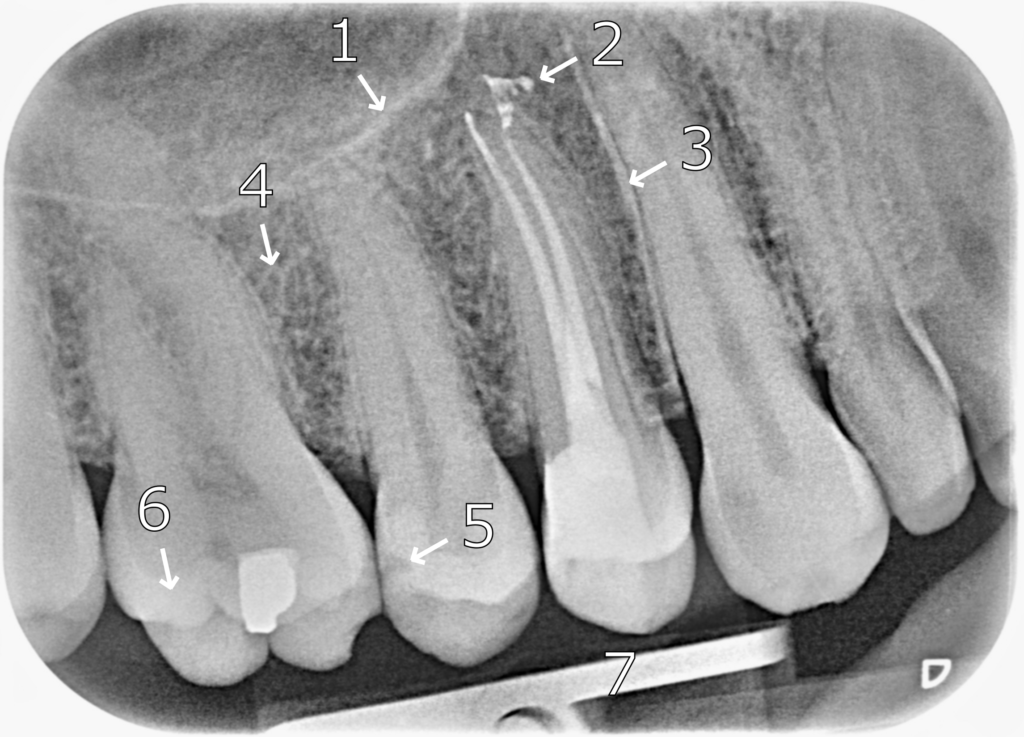

RADIOGRAPHIC ANATOMY

- Maxillary sinus floor.

- Extruded gutta-percha.

- Lamina dura.

- Bony trabecula.

- Internal restorative void.

- Enamel of the disto-lingual cusp of the maxillary first molar.

- Film holder